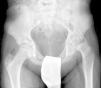

Mooney et al.43 realizaron una encuesta entre los miembros POSNA para valorar el manejo de la ECF. El 57% de los encuestados aconsejaban un tratamiento urgente (menor de 8 h), el 31% un tratamiento preferente y un 12% una reducción electiva. La reducción incidental era el método preferido por el 84% de los encuestados, mientras que el 11,8% preferían la reducción manipulativa formal (completa). El 64,6% desaconsejaba la descompresión capsular como parte del tratamiento de las ECF inestables y la fijación con un tornillo fue utilizada por el 57,4% de los encuestados, mientras que la fijación con 2 tornillos lo fue para el 40,3%. El riesgo de desarrollar una ECF contralateral en un paciente con ECF unilateral es de 2,335 veces mayor que el riesgo de una ECF inicial44, por lo que algunos autores aconsejan la fijación profiláctica contralateral considerando otros parámetros (edad, sexo, estado endocrino, preferencias del enfermo-familia…). A pesar de la evidencia científica de la fijación profiláctica contralateral, la mayoría de cirujanos que respondieron a la encuesta no optaron por este tratamiento43 (figs. 7 y 8).